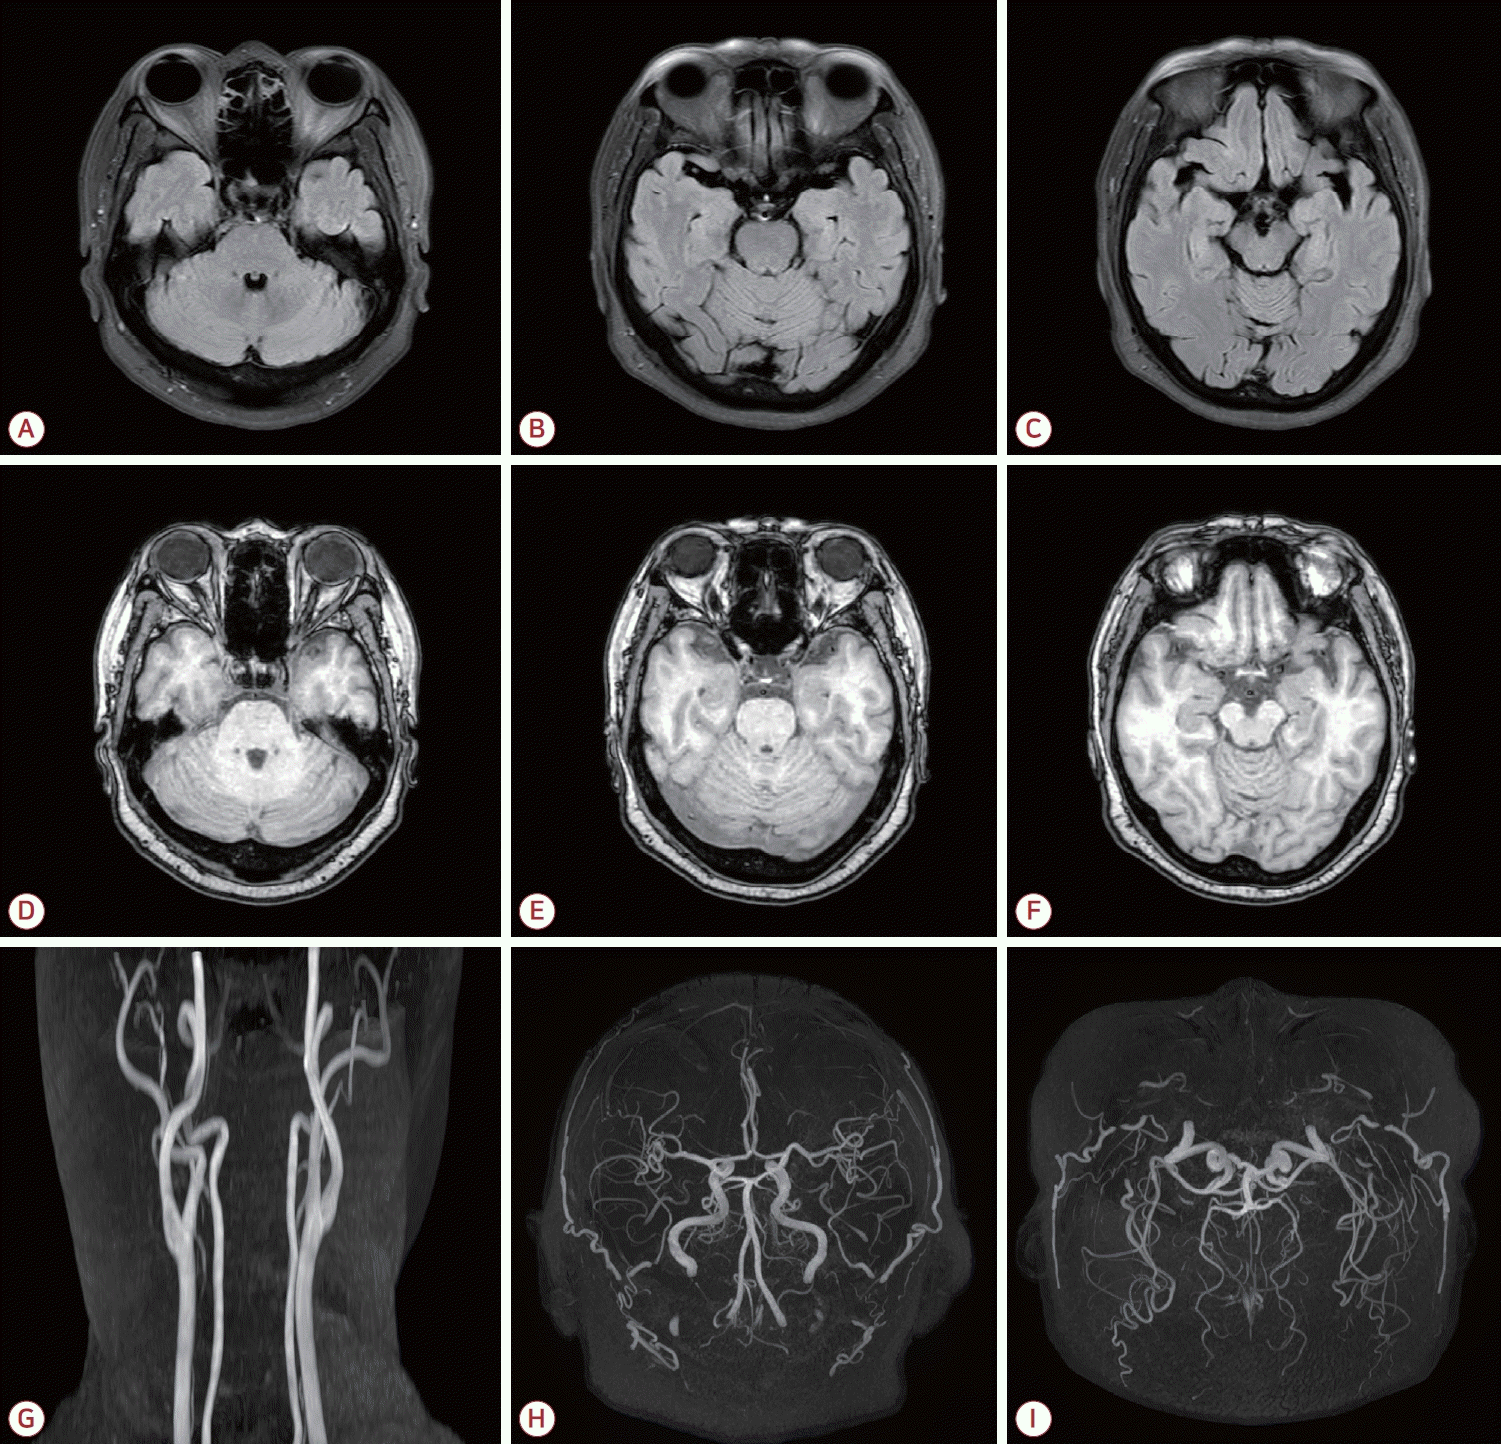

67세 여자 환자가 6개월 전부터 심화된 기억력장애를 주소로 2024년 7월 병원을 방문하였다. 음주와 흡연은 하지 않았고 10개월 전에 발생한 고혈압으로 투약 중이었다. 가족력에서 특이 소견은 없었다. 환자는 13년 전에 장기간 기침 후 객혈이 있었던 적이 있었으며 8년 전 기침이 심해지고 이비인후과에서 부비동염 진단을 받은 바 있다. 11개월 전 두통과 종아리 부위 근육통을 주소로 신경과에 내원하였고 당시 시행된 뇌자기공명영상(magnetic resonance imaging, MRI)과 뇌자기공명혈관조영(magnetic resonance angiography, MRA)을 시행하였으며 특이 소견은 없었고(Fig. 1) 신경전도 검사에서 신경병증의 전기생리학적 증거도 없었다. 내원 10개월 전 3주 동안 지속되고 있는 기침, 기침 시 심한 흉통, 양측 종아리 부위 통증, 양측 발등의 발열감, 간헐적 두통, 발열을 주소로 응급실에 내원하였고 류마티스내과 입원 후 혈액 검사에서 MPO-ANCA 135 IU/mL, 백혈구 7,700/μL, 호산구(eosinophil) 백분율은 0.9%로 임상적으로는 미세다발혈관염인 MPO-ANCA연관 다발혈관염으로 진단되었다. 그 이후 타 병원에서 싸이클로포스파마이드(cyclophosphamide)와 고용량 스테로이드 병합 치료 중이었다.

Figure 1.

Brain MRI performed prior to the diagnosis of MPO-ANCA-associated vasculitis demonstrates no abnormal signal on FLAIR images (A-C) or T1-weighted images (D-F). Magnetic resonance angiography (MRA) reveals no significant stenosis or vascular abnormality on carotid MRA (G) or intracranial MRA (H-I). MRI; magnetic resonance imaging, MPO; myeloperoxidase, ANCA; antineutrophil cytoplasmic antibody, FLAIR; fluid attenuated inversion recovery.